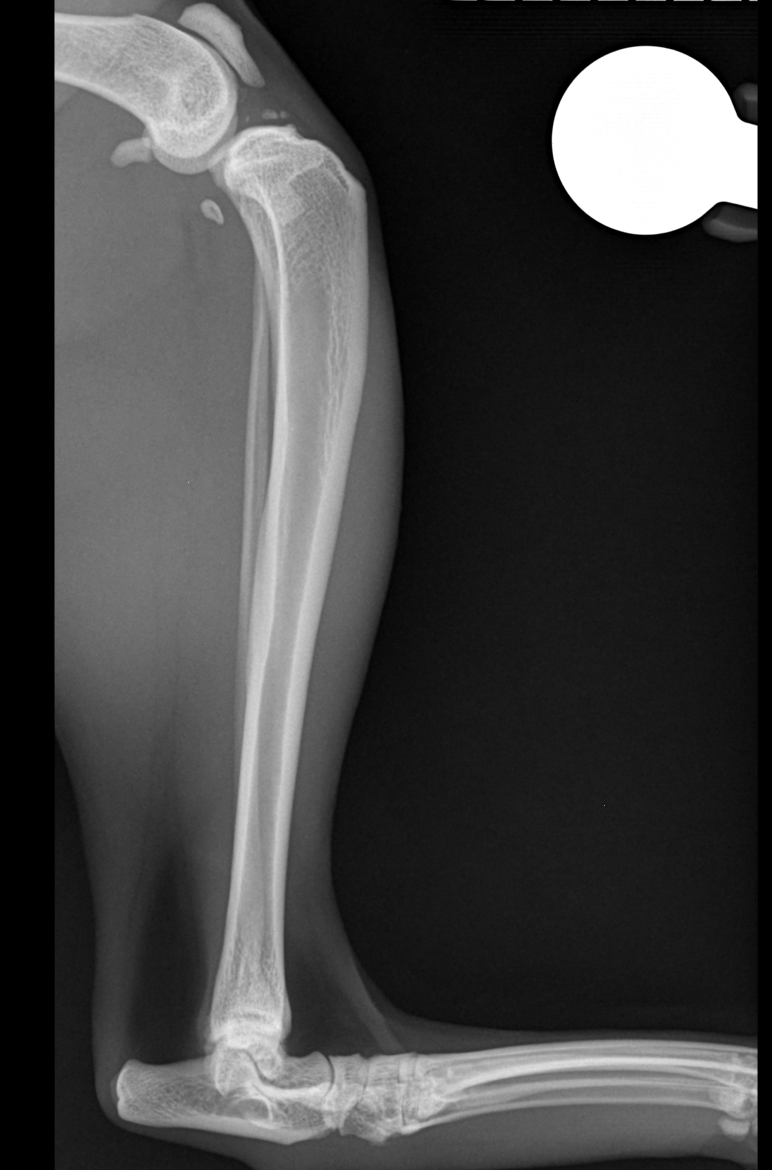

Wie beim Hund kann auch die Katze mit der TPLO-Technik operiert werden. Die Methode stabilisiert das Knie, lindert Schmerzen und ermöglicht eine schnelle Genesung.